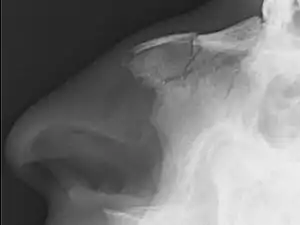

| Plain X-ray showing a nasal fracture | |

Nasal fractures are usually identified visually and through physical examination.[1] Medical imaging is generally not recommended.[1][3] A priority is to distinguish simple fractures limited to the nasal bones (Type 1) from fractures that also involve other facial bones and/or the nasal septum (Types 2 and 3). In simple Type 1 fractures X-Rays supply surprisingly little information beyond clinical examination. However, diagnosis may be confirmed with X-rays or CT scans, and these are required if other facial injuries are suspected.[3]